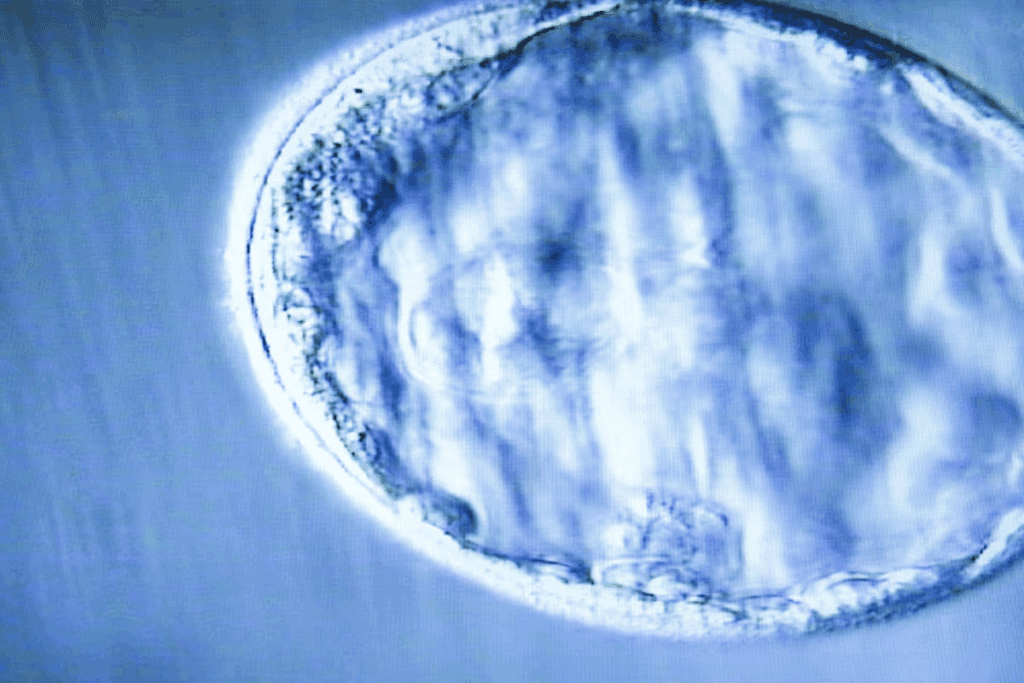

A blastocyst’s size and cellular structure give us clues about its development and health. This stage is key in early embryo growth, happening 5-6 days after fertilization.

The embryo grows into a structure with a fluid-filled center. It’s surrounded by two cell groups: the inner cell mass and the trophectoderm.

The Three Fundamental Layers of a Blastocyst

The blastocyst has three main layers: trophoblast, inner cell mass, and blastocoel. Each layer has a unique role in the growth of the embryo. Knowing about these layers helps us understand how the blastocyst develops.

Structural Organization Overview

The blastocyst’s structure is made up of three key layers. The trophoblast is the outer layer. It will help form the placenta and other tissues. Inside the trophoblast, the inner cell mass holds cells that will become the embryo. The blastocoel is a fluid-filled space in the blastocyst. It’s important for the embryo’s growth and development.

Visualization Through Modern Imaging Techniques

Modern imaging has changed how we see the blastocyst and its layers. Time-lapse microscopy lets us watch the blastocyst grow in real-time. This gives us important insights into its layers.

These advanced imaging methods have greatly improved our understanding of the blastocyst. They help us see how the layers work together. This knowledge is key for understanding why some embryos implant better than others.